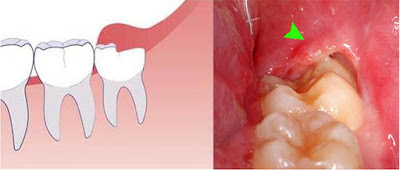

Viêm lợi trùm bao lâu thì khỏi là câu hỏi mà nhiều người thắc mắc. Viêm lợi trùm là tình trạng thường thấy khi răng khôn mọc lệch hay mọc ngầm, nếu không điều trị kịp thời sẽ gây ra những biến chứng nguy hiểm. Vậy viêm lợi trùm có tự khỏi không? Bao lâu thì khỏi? Cùng tìm hiểu qua bài viết dưới đây.

| Tình trạng viêm lợi trùm răng khôn* |

Răng khôn là chiếc răng mọc cuối cùng trong cung hàm, vì phải mọc chen lấn nên chiếc răng này thường thường mọc xuyên vào vị trí khác, mọc lệch khỏi hàm khiến cho phần nướu xung quanh bị sưng tấy, đau nhức dữ dội.

Viêm lợi trùm bao lâu thì khỏi? Viêm lợi trùm có thể tự khỏi khi răng khôn mọc thẳng, phát triển bình thường. Tuy nhiên, trường hợp này là rất ít và thường gây ra những cơn đau nhức kéo dài. Trong những trường hợp viêm lợi trùm răng khôn, bác sĩ thường sẽ chỉ định cắt lợi trùm, hoặc nhổ răng khôn nhằm tránh những biến chứng nguy hiểm.